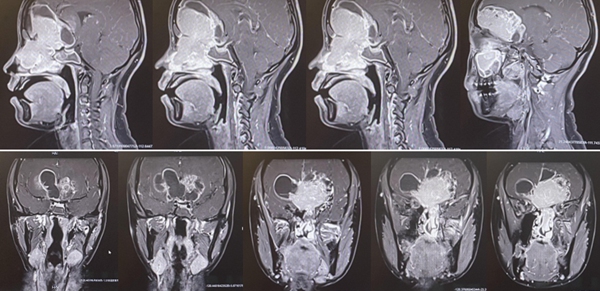

小于術前的磁共振,能夠清晰看到巨大的腫瘤,像豎起的“啞鈴”一樣,連通顱內和鼻腔。重慶醫科大學附屬第二醫院供圖

神經外科主任謝宗義接診后,立即意識到該腫瘤的復雜性和危險性:它像一個巨大的“啞鈴”,一個頭長在顱內,嚴重壓迫腦組織;另一個頭掛在鼻腔,幾乎把鼻腔填滿;中間的連桿則破壞顱底,把顱底骨頭侵蝕出一個大洞,牢牢卡在里面。仔細詢問后,謝宗義得知小于已經出現了頭痛、厭食、視力下降等顱內高壓的危險信號,病情兇險。